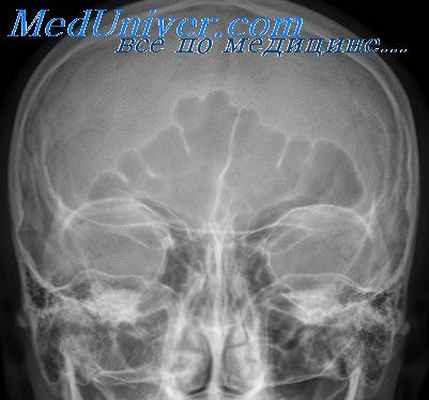

Рис. 8. Хронический гайморит. Рентгенограмма околоносовых пазух. Слева в верхнечелюстной пазухе определяется широкая пристеночная тень утолщенной слизистой оболочки (1). Справа – пневматизация пазухи отсутствует (2).